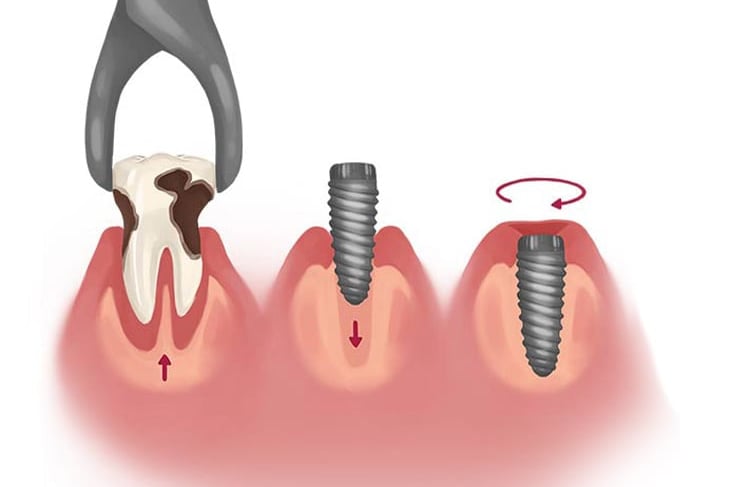

Consiste en insertar un tornillo de titanio en el hueso de la mandíbula o el maxilar, que actúa como raíz del diente y sirve de soporte para una corona, puente o prótesis dental.

Implantes Dentales

Se colocan implantes inmediatamente después de la extracción dental, reduciendo el tiempo total del tratamiento y manteniendo la estructura ósea.

Colocación de implantes inmediatos post-extracción